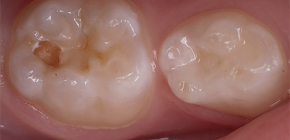

Em detalhes sobre as cáries ocultas, bem como seus exemplos na foto

A cárie não é apenas manchas escuras nos dentes brancos e saudáveis. Em muitos casos, essa doença se desenvolve de tal maneira que o dono dos dentes, e às vezes até o dentista, não percebe. Acontece que a cárie se faz sentir apenas pela dor na polpa afetada e, nesse estágio, já é necessário remover o nervo do dente e fazer um grande preenchimento. Nesses casos, eles falam sobre cárie oculta - uma forma da doença na qual ela não é visível durante um exame visual. Falaremos mais sobre cáries ocultas e seus recursos mais tarde ...